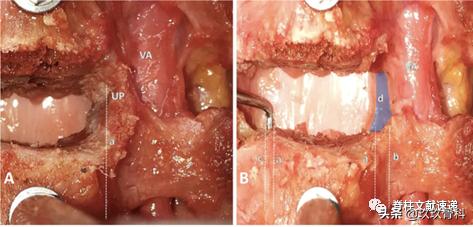

文章认为钩突尖可以作为开槽的解剖标志,开槽后距离横突孔约2mm距离。下图为尸体解剖图片,a开槽线位于钩突尖内侧,b横突孔内缘,c椎弓根内缘投影,神经钩紧贴椎弓根。